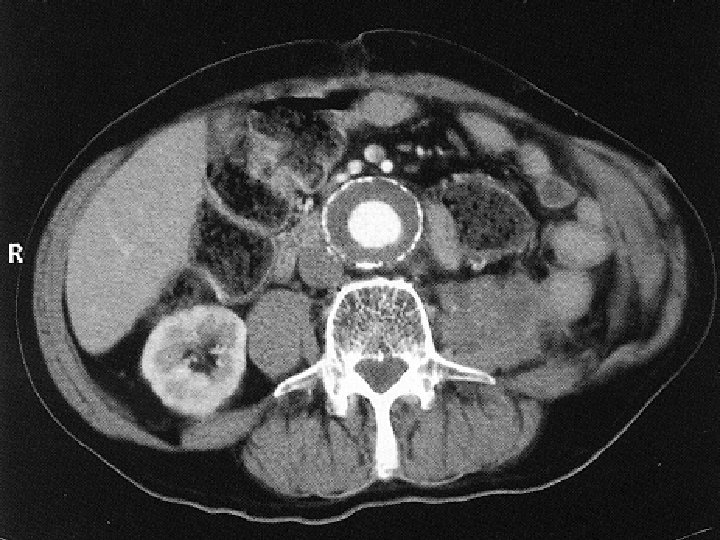

A CTA leggyakoribb alkalmazása n Mellkasi és hasi aorta, valamint iliaca rendszer vizsgálata aneurysma esetén a CTA pontos választ ad: - nagyság – növekedés - kiterjedés – kiinduló erek érintettsége - trombotizáltság - ruptura fennállása – haematoma